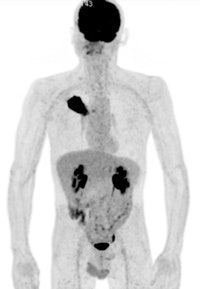

A 50-year old male patient with NSCLC stage pT2b pN2 cM0, imaged with FDG-PET/CT-MR. On coronal PET maximum intensity projection (MIP) image, an FDG-avid tumor in the right upper lobe and a mediastinal lymph node metastasis are seen. All images courtesy of Dr. Martin Huellner.For many years, PET/CT has been the standard modality for staging NSCLC patients. So, before PET/MRI can supplant it for this application, some basic clinical questions need to be addressed, said lead author Dr. Martin Huellner from University Hospital Zurich.

"One of them is if PET/MR imaging is equal to or superior to PET/CT in certain cancer entities or organs," he said during his presentation. "Second, which fast MR imaging techniques are most appropriate to achieve high diagnostic accuracy, given the comparably short PET image acquisition time of 10 to 15 minutes?"